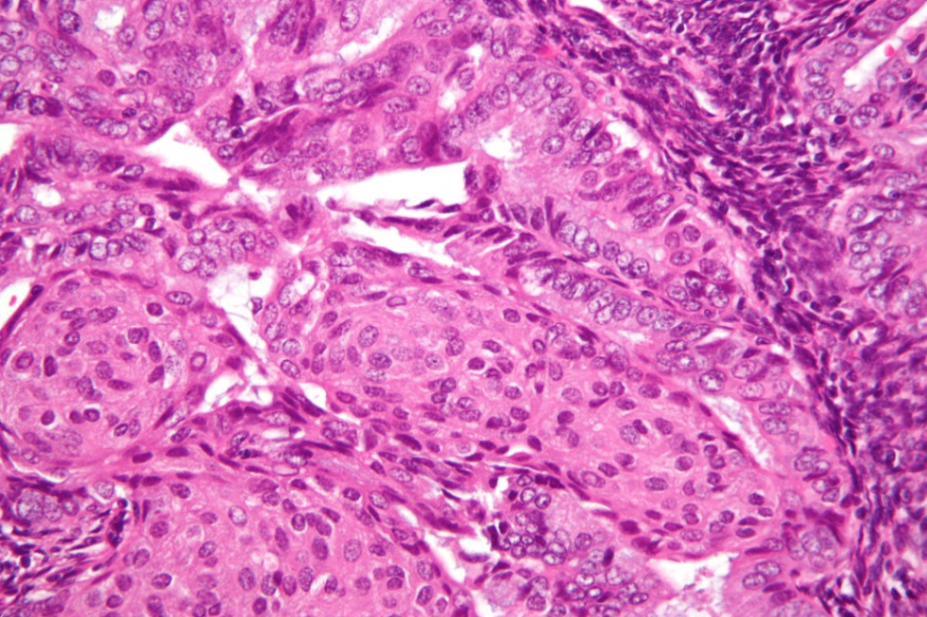

(2) 장액샘종 (serous endometrial carcinoma)

• 고등급 자궁내막암에 속하며 악성도가 높고 예후가 나쁨

• 위축성 자궁내막이 위험요인 → 폐경 여성에서 발생

• p53 유전자 돌연변이와 높은 연관성을 보임

• 조직학적 특성:

- 상피성 세포(serous cell)가 자궁내막에서 증식

- 구성 세포는 다양한 형태를 가지며 핵이 비정상적으로 크고 불규칙함

- 세포가 고밀도로 배열되며, 거품처럼 보이는 세포질을 가짐

• 자궁내막을 넘어 자궁 근층이나 인접한 조직으로 침습할 수 있음

Serous endometrial carcinoma, Wikipedia Commons